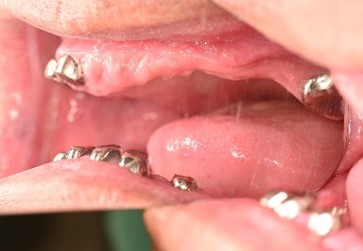

女性Tさん 60代(マグネット式入れ歯)

主訴

歯周病やむし歯の悪いところは、全部治したい。

治療内容

上1本、下1本は、歯周病が進行し保存することが出来ず抜歯。残っていた全部の歯に被せものがしてあり、そのほとんどが2次カリエスになっていました。上6本のうち4本、下7本のうち4本を利用し、マグネット式入れ歯を装着しました。

所感

残っている歯が、すべて頑丈な状態ではありませんでした。また、嘔吐反射が激しかったので、口蓋の床を短くしてほしいという要望がありました。こういう時に最も効果的な方法の一つにマグネットを利用した総義歯があります。患者さんにマグネット式入れ歯をお勧めしたところ、是非、マグネット式入れ歯でお願いしますという事になりました。治療後「入れ歯の密着度がよく、自分の歯のように使いこなしたいと思います。仕上がりがすごくきれいで気に入ってます。先生も衛生士の方も説明がわかりやすくて良かったです。」というお話を頂き、スタッフ一同とても嬉しくなりました。